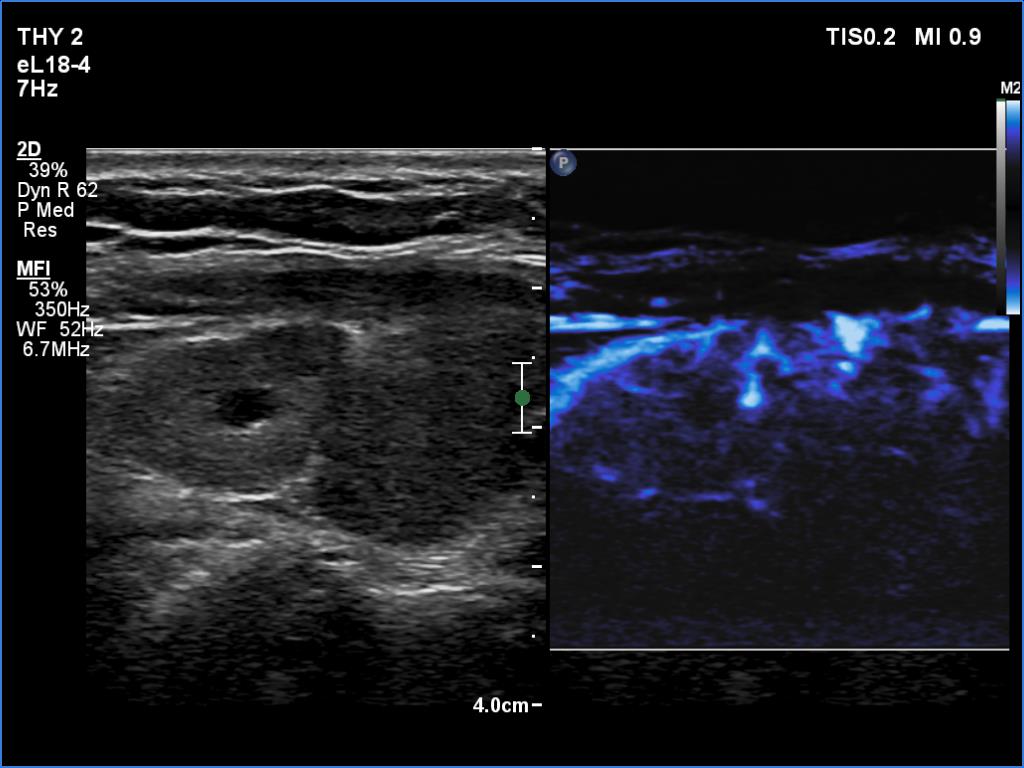

The operated thyroid - case 1388

Five years after the surgery (ultrasonographic picture 7)

Left lobe, longitudinal scan, microflow imaging. A relatively large vessels runs at the ventral surface of the lobe.